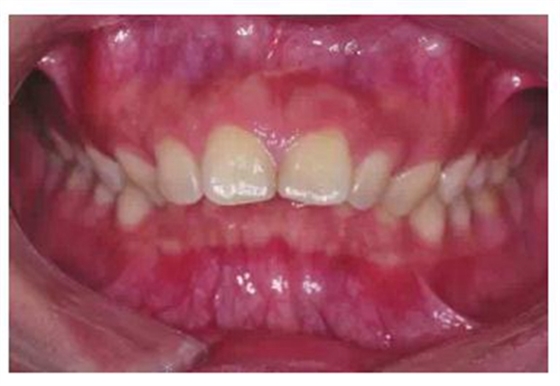

由于有很多患者在微笑時(shí)“頰廊”會(huì)比較明顯(圖2),這種情況往往預(yù)示著其上牙弓狹窄或上頜后牙過(guò)于舌傾(圖3),從而影響了微笑的美觀,正畸時(shí)有必要直立上頜后牙,這樣就可以創(chuàng)造飽滿的微笑,這類病例可以考慮選擇上頜前磨牙的零度轉(zhuǎn)矩,有效實(shí)現(xiàn)上頜后牙的直立。

圖2 患者在微笑時(shí)“頰廊”

圖3 存在“頰廊”者的口內(nèi)情況